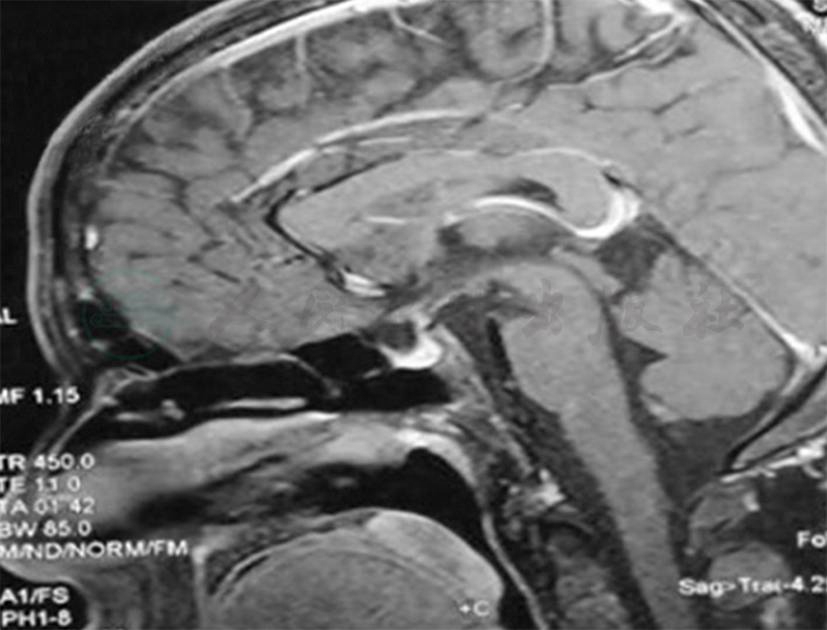

头部鞍区磁共振增强:垂体柄局部结节样增粗(图6)。

图6 鞍区磁共振

放射科:临床及影像学表现符合结节病,Ⅰ期和Ⅱ期结节病可以有对称性肺门纵隔淋巴结肿大,Ⅲ期结节病肺内出现结节和纤维化病变,纵隔淋巴结消失,Ⅳ期结节病出现蜂窝肺,并且结节病非常容易累及颅内垂体,导致尿崩症,该患者完全符合。

内分泌科:患者颅内垂体部位可以看到结节状增粗,临床表现为尿量明显增多,9 000ml/24h,表现为尿崩症,禁水试验支持尿崩症诊断,虽然还有一些检查没有完善,但是结合头颅影像学特征,考虑垂体增粗受累,与肺内病变为同一种疾病导致,用一元论解释,考虑结节病。